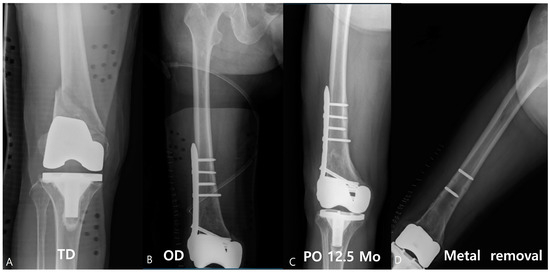

An 83-year-old female patient showed multiple screw breakages at the junction of the screw head and neck after the removal of the plate (Figure 2). An 81-year-old male patient who was reduced by LCP for periprosthetic fractures remained with two broken screws after the removal of the plate (Figure 3).

Figure 3.

Approximately 81-year-old male patient visited with a periprosthetic fracture after total knee arthroplasty (A); 10 holes of LCP were used for the reduction (B). After union, the plate was removed at 12.5 months, and the two screws were broken (C,D).